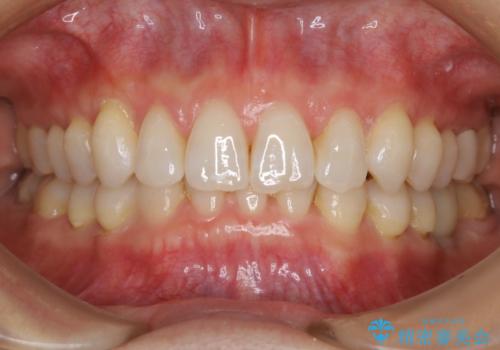

【抜歯】矯正治療とインプラントで正常な噛み合わせを実現

- 30代 女性

- マウスピース(インビザライン)

- 2年2ヶ月

- 元々は矯正治療を主訴にご来院されました。

治療を始めるにあたり、精密検査を受けていただき全体の状況を把握したうえで矯正治療の計画を立てることとなりました。

その過程で左下の6番目の歯は治療が必要な状態であることが分かり、被せ物を外して内部を確認してみると根が破折してしまっていることが判明しました。

歯が深い位置で破折している場合は基本的には抜歯が選択されます。

様々な治療プランを患者さんと相談させて頂き、最終的にインプラントで噛み合わせを回復させていくこととなり、まず悪くなっている歯を抜歯することから開始しました。